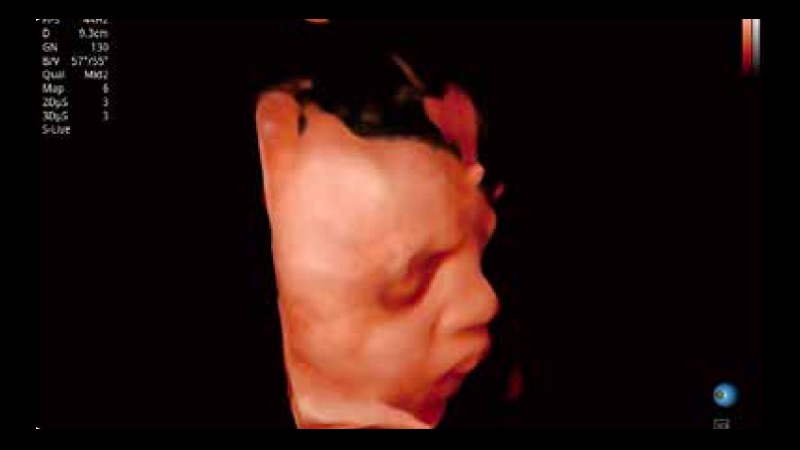

開立醫(yī)療通過不斷的技術(shù)創(chuàng)新,為大眾的生命健康提供持續(xù)關(guān)愛。P12 Plus采用全新一代超聲成像平臺,新平臺旨在將真實(shí)還原組織解剖結(jié)構(gòu)作為首要目標(biāo)。平臺采用全新集成化硬件模塊,搭載新一代芯片,系統(tǒng)性能得到大幅提升,為您的診斷提供了豐富的臨床信息。優(yōu)異的圖像表現(xiàn),豐富的探頭配置,全面的應(yīng)用功能,為您日常診斷提供了可靠的助手。

P12 Plus

彩色多普勒超聲診斷系統(tǒng)